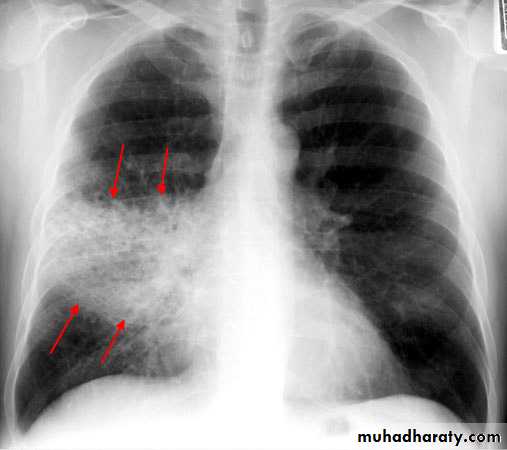

Staphylococcus aureus occur in association with debilitating illness, or complicating influenza.

Multiple lobe involvement, cavitation, pneumatocoele and abscess formation are characteristic.

A chest X-ray is usually sufficient to confirm the clinical diagnosis of pneumonia.

Chest X-ray helps in:• Differentiating CAP from other diagnosis

• Provide information about severity (cavitation and multilobar involvement)

• Detects complications (pleural effusion or abscess formation).

• It can occasionally suggest an aetiological agent (pneumatocoele in Staphylococcus aureus pneumonia).